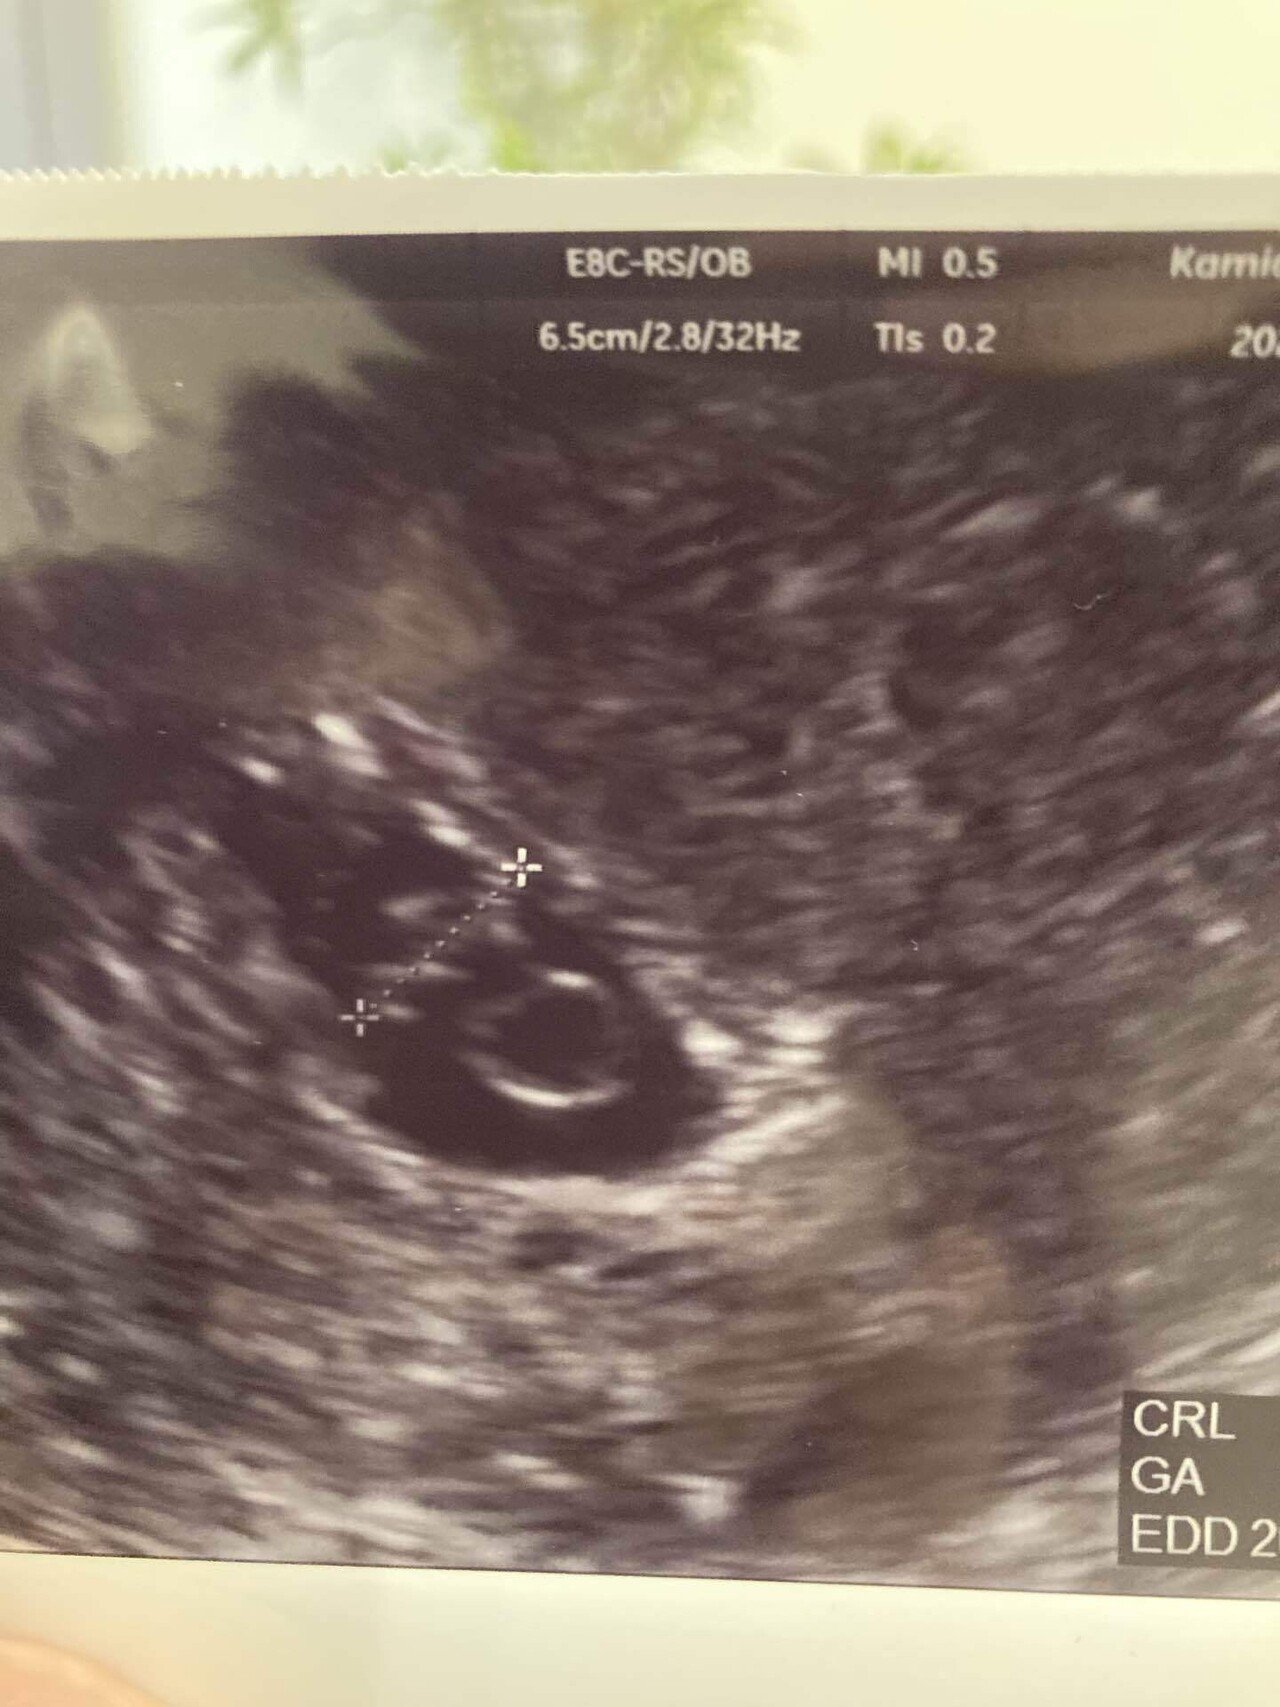

Web本日病院受診をし、胎嚢確認はできましたが小さいと言われました。 推定5週4日で69mmでした。 小さいから流産の可能性もある、 このまま成長してくれれば心配はなくなる また2週間後に来てくださいとのことでした。 今日妊娠発覚後初めての診察でした。 最終月経日から数えると5週3日目です。 胎嚢確認はできたのですが、47mmでした。 先生には「小さいね~」とWeb 「胎嚢サイズ小さい? 大丈夫? 」ってこと。 ネットで検索してみると、 妊娠5週の胎嚢の平均サイズは、10mm~25mm程度と書いてある。 三重大学医学部の資料による

Web 6週の胎嚢の大きさは約2cm 胎嚢の中に卵黄嚢が見える場合も多い 胎芽が確認できることもある 心拍が確認できることもある 参考リンク たまひよ エコーで見ても心臓が動いWeb ネットで調べても私ほど胎嚢が小さい人がいなかったので調べれば調べるほど不安は募りました。 しかし、その3日後の検診で99ミリまで大きくなっており心拍も確認でき、 今は最初29?だった子供は生後7ヶ月になり毎日元気に遊んでいます。 本当に不安ですよね。 しかし、さくらんぼさんのお腹の中では小さな小さな命ががんばって生きようと生まれてくるWeb 胎嚢が5w1dで53ミリでした。 そして6w2dで80ミリでした。 全然大きくなってないし小さい。 。 もちろん中身などなにもありません。 まだ確定は出来ないとまた1週間後に診察です。 ほんとに少しでも希望はあるのでしょうか。 体外受精のため日数は正確です。 通報する この質問への回答は締め切られました。 質問の本文を隠す A 回答 (1件) 最新から表

Web体外受精 (IVF/ICSI共に)での妊娠は、初期の胎嚢が小さいという事が全体の3〜4割あるようです。 ※諸説あり 私自身、陽性判定をもらい、 5w2d の胎嚢確認の時点で 53mm (厳格に計測すWeb そうやね、(カルテを見て)6週と4日だけど胎のうの大きさは4~5週程度です。 」とあっさりそれだけ。 もうだめだろうと、落ち込んでいます。 今まで2回流産していますWeb 胎嚢小さいでしょうか? 3日前ほどに検査薬陽性でたので 本日受診して参りました。 無事胎嚢が確認でき、医者には特に指摘もなく、ではまた2週間後に来て下さい〜と言

Web 胎嚢が小さい原因として考えられる可能性 内診後は先生から胎嚢が小さいことに関する説明があり、可能性として2つの原因を挙げました。 流産 最終生理日から計算するとWeb 赤ちゃんのサイズは44mmで、やはり2週間ほどサイズが小さいようでした。 (胎嚢のサイズは教えてもらわずじまいだったので、サイズ不明です。 ) 検診4回目(修